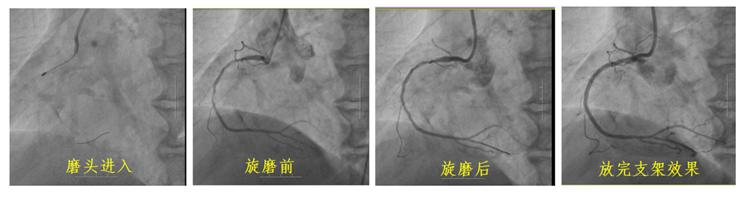

長春國文醫院開展IVUS導航冠脈旋磨術 成功治療冠狀動脈嚴重鈣化病變

冠狀動脈鈣化因其致密堅硬的病變特征,長期制約著心血管介入治療效果。長春國文醫院心血管內科團隊引入冠狀動脈旋磨技術,在血管內超聲(IVUS)實時導航下,以每分鐘15萬轉旋磨技術精準粉碎鈣化斑塊,成功為一名右冠狀動脈100%閉塞的73歲患者實現血管再通。該技術的成熟應用,標志著醫院在旋磨技術處理復雜鈣化病變的臨床可靠性,為更多心血管疾病患者帶來康復希望。

冠狀動脈旋磨術作為一項先進且高難度的冠脈介入治療技術,在處理冠狀動脈嚴重鈣化病變方面具有獨特優勢。其基于精確的“差異切割”原理,通過高速旋轉的旋磨頭,精準地對鈣化或纖維化的動脈硬化斑塊進行祛除,同時巧妙避開有彈性的血管組織及正常冠狀動脈,從而極大地降低對血管中膜的損傷風險。該技術具有精確性高、安全性強、效果持久以及適用范圍廣等顯著特點,能夠有效減輕冠脈狹窄程度,顯著改善心肌供血狀況,為冠心病等心血管疾病的治療開辟新路徑。